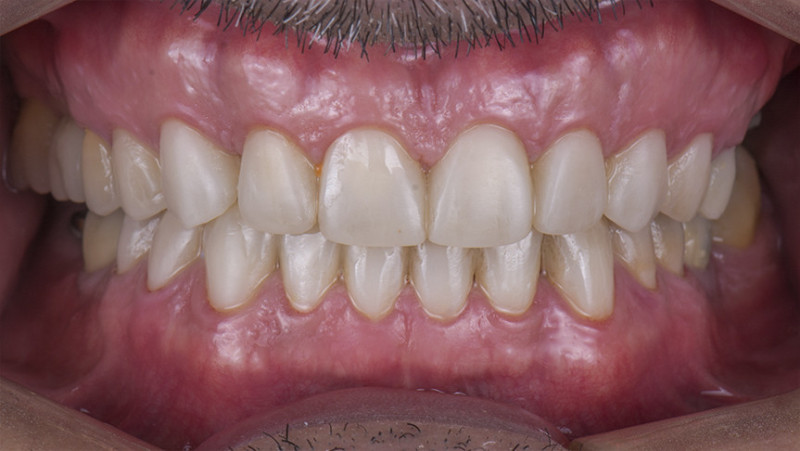

На странице представлено портфолио стоматологий Нижнего Новгорода с фото работ до и после установки зубных коронок. Показываем, как можно полностью восстановить форму разрушенного зуба и эстетичный вид улыбки. На странице собраны разные клинические случаи восстановления одиночными коронками из металлокерамики, циркония или керамики. Изучите результаты до и после процедуры и выберите подходящую клинику для восстановления зуба в Нижнем Новгороде.

Изготовили и установили 22 керамические коронки EMAX и 6 виниров на нижнюю челюсть. Провели пластику десны в области 22 зуба. Устранили сильную рецессию десны в области имплантата, установленного в другой клинике.